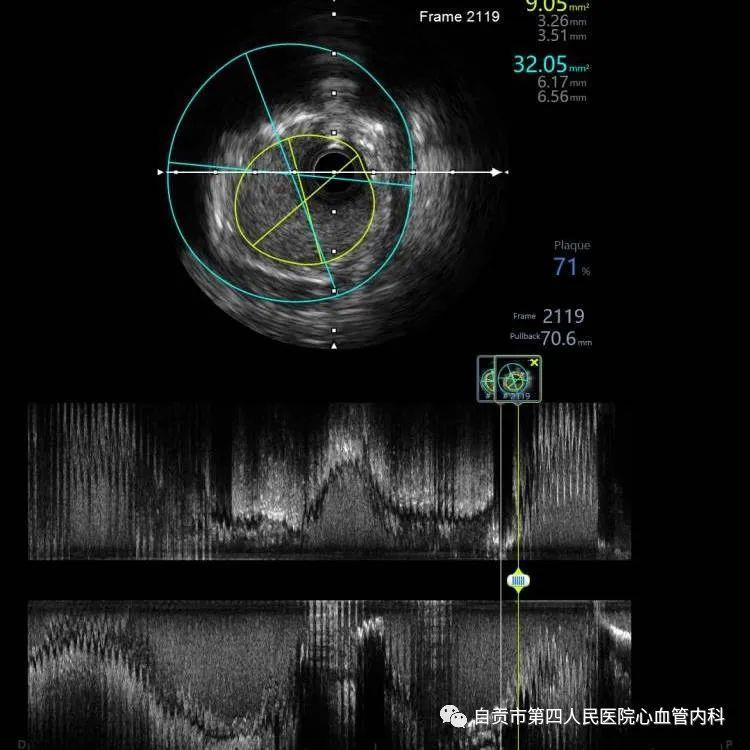

作者:汤勇 自贡市第四人民医院心血管内科引进又一利器“冠脉内超声检查(IVUS)”,助力冠心病精准治疗,目前我国冠心病发病率呈现一个高发的态势,冠心病的发病年龄也呈年轻化的趋势,20-30岁的人群发生急性心肌梗死也不少见。 ![]() 冠脉完全闭塞导致心梗 ![]() 急诊手术成功开通血管 药物加冠脉支架治疗是治疗冠心病的常规治疗手段,我们通常选择冠脉造影对患者的冠状动脉血管检查,由于冠脉造影显示的血管图像是二维图像,并不能完全真实地反映患者冠脉病变的实际情况,有可能造成不必要的支架植入,判断支架的大小完全依赖经验与造影图像,也有可能造成支架大小,长度选择不当。 ![]() ![]() 为了更精准对冠心病患者治疗,优化支架植入,减少支架植入的并发症的发生。 ![]() IVUS图像 ![]() 造影显示需要支架治疗 我院引进了美国波科公司的冠脉内超声检查(IVUS)检查设备,对患者的冠状动脉进行实时检查,为临床医生在对冠心病患者是否需要支架治疗,支架合理应用提供更为准确得信息。 ![]() 我们有一位患者在西昌某院因心肌梗死,行右冠状动脉支架治疗,当时冠脉造影检查提示右冠状动脉支架有一重度狭窄,建议择期再行支架治疗,患者慕名来我院来进一步检查。从冠脉造影的情况确实需要进行支架治疗,由于患者年轻,已安置支架4枚,故决定对患者进行冠脉内超声检查(IVUS)检查。 ![]() 支架局部膨胀不全 ![]() 冠脉内超声检查(IVUS) ![]() 支架直径恢复正常 患者冠脉内超声结果提示管腔面积能够满足心肌血供,且病变邻近血管直径大于5mm,不适合支架治疗。故建议其药物治疗,必要时复查造影。另外该患者造影显示已安置的支架显示膨胀不全的可能,进行冠脉内超声检查后显示支架内有明显膨胀不全的征象,故予以球囊扩张,支架管腔直径恢复正常。 在今后的冠心病治疗上,冠脉超声检查将发挥更大的作用,特别是复杂病变,左主干病变,钙化病变,闭塞病变方面,将大大减少冠脉介入治疗的并发症,再次支架治疗的发生率降低,将大大提高我院冠心病的精准治疗水平。 ![]() ![]() |